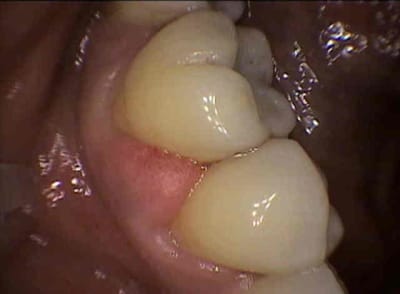

Apparition de l'abces en 2 jours , me dit qu'elle passe les brossettes sauf depuis l'inflammation.

Qu'en pensez vous , quelle peut etre l'origine de cet abces ?

perso je pense à une blessure avec la brossette ou autre chose ( aliment )mais si tu dis qu'elle est nerveuse ne bruxe t elle pa ou ne crispe t elle pas occasionnant des mobilites legères mais suffisantes pour des tassements alimentaires....

Problème de point de contact?

en plus la 6 présente une légère fissure de l'émail au niveau de la "fossette"qui pourrait provoquer un tassement alimentaire

J'oserais aussi ajouter qu'elle est hypo droite en PIM et bloquée dans le jaune (possible aussi sur le bleu, tout dépend sur quelle dent maxillaire elle articule cette 6) sur l'oeil droit bouche ouverte